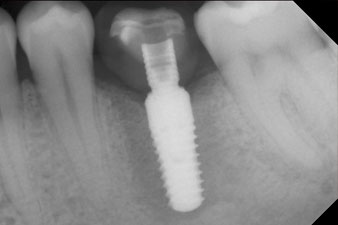

Après cicatrisation des tissus mous, la stabilité de l’implant a été mesurée une nouvelle fois avant la pose de la restauration prothétique.

Les deux valeurs étaient pratiquement inchangées, situées entre la plage moyenne et la plage haute - la valeur la plus basse étant toujours utilisée comme valeur de référence qui détermine le traitement.

Par conséquent, il a été possible d’enregistrer une ostéo-intégration réussie et une stabilité biologique correcte, permettant également de prendre une empreinte durant la même séance.

Les dernières photos montrent la couronne composite monolithique retenue par une vis une fois mise en place et la radio de contrôle (Fig. 9 et 10) (6).